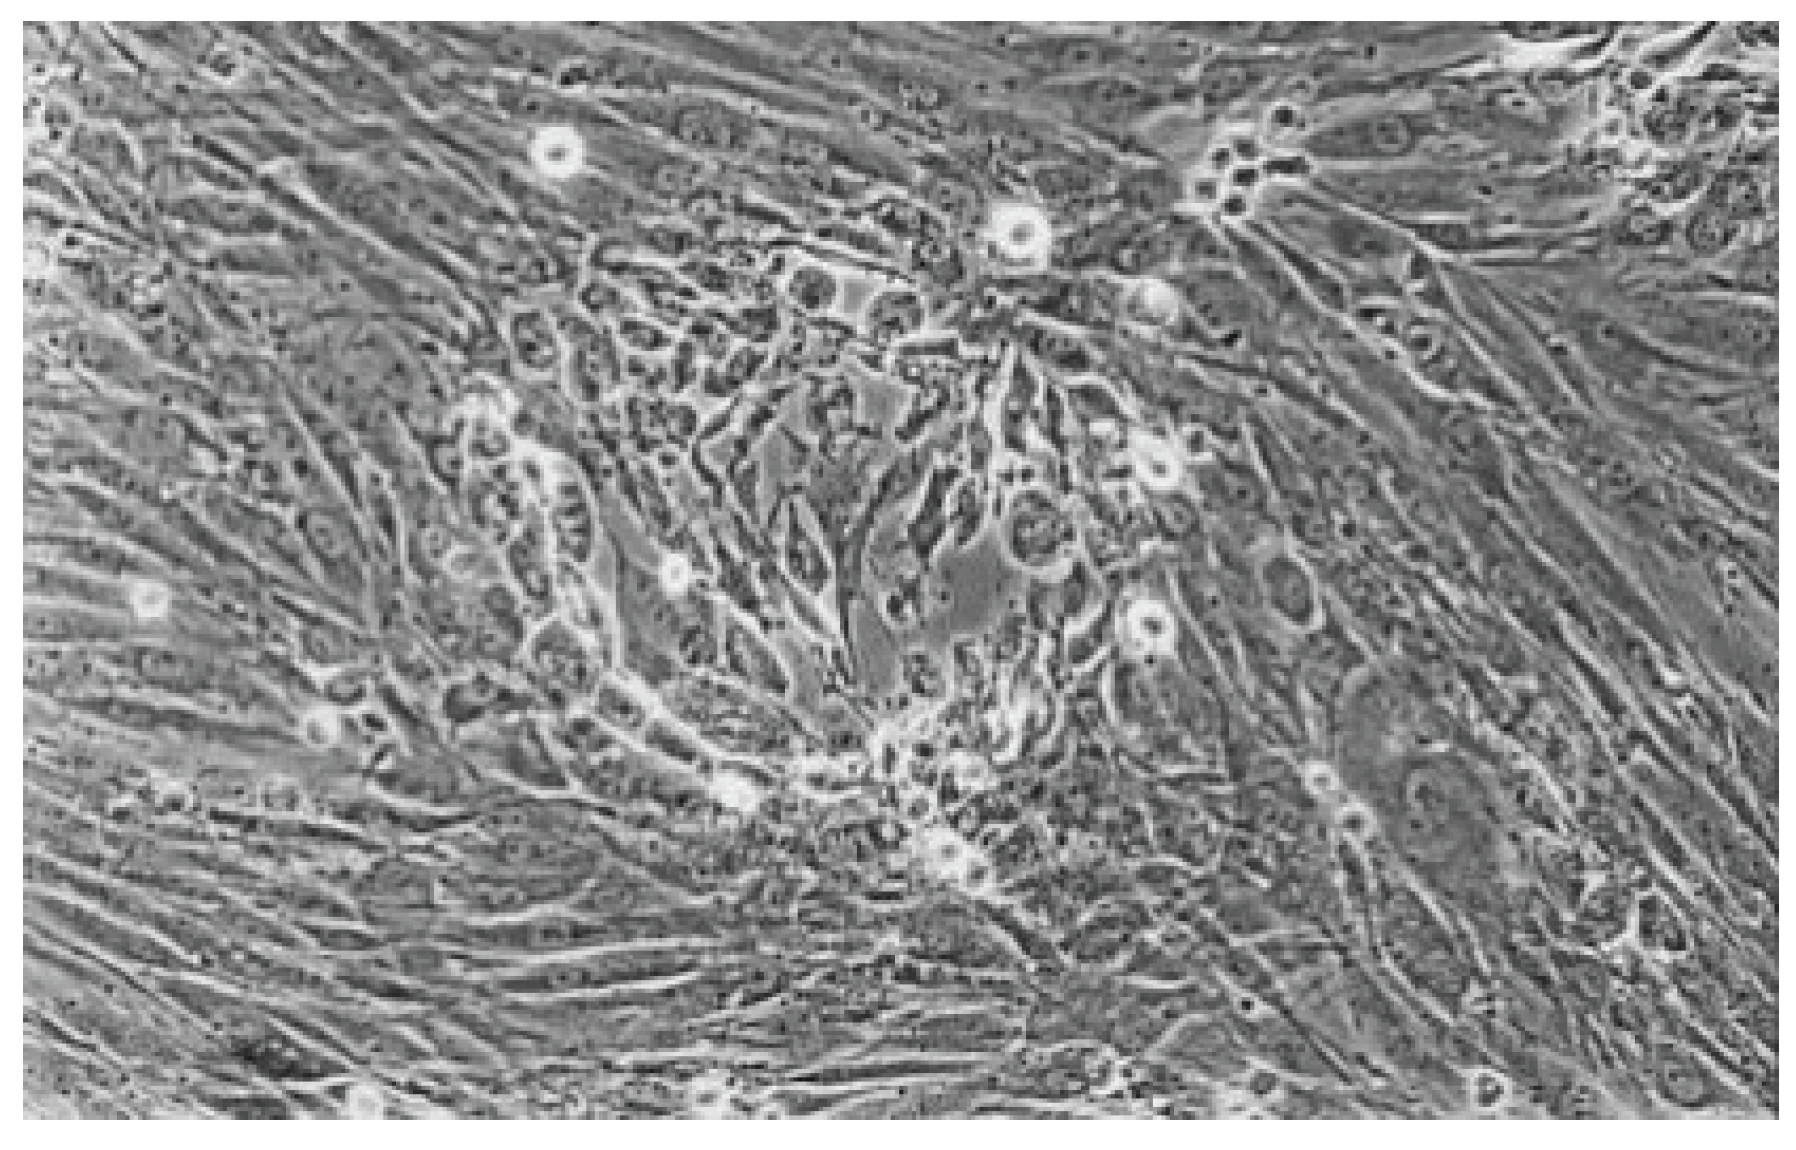

The qualitative evaluation is shown in Table 2, Table 3, Table 4, Table 5, Table 6 and Table 7. Figure 6, Figure 7, Figure 8, Figure 9, Figure 10, Figure 11 and Figure 12 depict the characteristic appearance of the cell cultures in the influence of the different dentin adhesive materials. The morphological phenotype of this cell line is characterised by spindle-shaped, long cells derived from the gingiva (HGPFC—human gingival primary fibroblast cells) representing human primary fibroblasts (pMF).

Figure 11. Rounded and viable fibroblasts can be found in the cell culture of Syntac (No. 5). The fibroblast lawn is much less dense than the cell control (100-fold magnification).